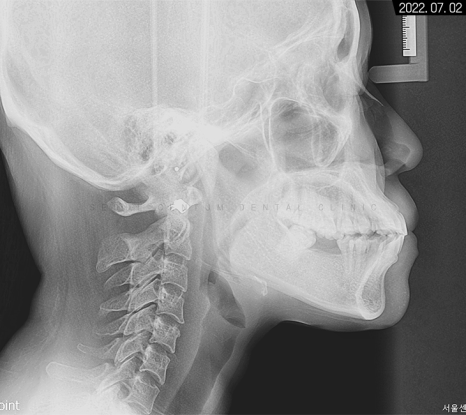

세팔로 사진으로는

잇몸과 치아 전돌 양상이 보이고

에스테틱 라인을 과하게 넘어가 있다는 것을

알 수 있었습니다.

계측점을 분석해 본 결과 정상 범주로 넣기 위해서는

치아 후방 이동이 상당히 필요한 경우였습니다.

뻐드러진 앞니 모양이 보이는데,

이 같은 상태면 앞니 사용이 좋지 않아

식사가 불편하고 아랫니가 잇몸을 자극해서

치주염까지 생길 수 있어 주의해야 합니다.